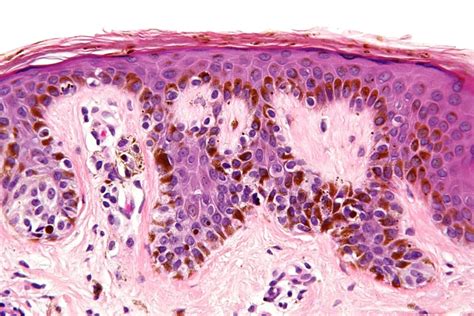

Understanding skin health is crucial for maintaining overall well-being. One condition that often raises concerns is Moderate Dysplasia Nevus. This term refers to a specific type of mole that exhibits moderate levels of dysplasia, a condition where the cells in the mole appear abnormal under microscopic examination. While not all dysplastic nevi are cancerous, they can sometimes develop into melanoma, a serious form of skin cancer. This blog post will delve into the details of Moderate Dysplasia Nevus, its causes, symptoms, diagnosis, and treatment options.

Moderate Dysplasia Nevus is a type of mole that shows moderate levels of cellular abnormality. These moles are often larger than common moles and have irregular borders and varied colors. The term “dysplasia” refers to the abnormal growth of cells, which can be a precursor to cancer. While not all dysplastic nevi progress to melanoma, it is essential to monitor them closely.

• Histopathology: The biopsy sample is analyzed by a pathologist to determine the level of dysplasia and rule out melanoma.